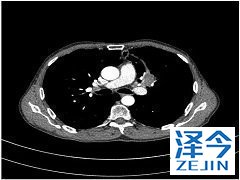

我们介绍了一例患有IV期肺腺癌的68岁男性的病例,其在外显子21(L861Q)中具有罕见的EGFR突变。这种疾病在他开始厄洛替尼(每日150毫克)后2年进展。使用经支气管肺活检,我们检测到外显子20(T790M)和外显子21(L858R)的其他突变。他接受了奥希替尼治疗(每日80毫克)并达到部分缓解。该病例证明了EGFR-TKI治疗后患有不常见EGFR突变的患者重复活检的价值。